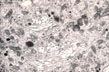

Cytoplasmic organelles Electron micrograph of a hepatocyte showing the cytoplasm with the various cytoplasmic organelles above described.

RER (rough) endoplasmic reticulum).Abundant and preponderant in zone 1 and 2 where the highest synthetic activity occurs,being the most oxygenated and nourished zones of the lobule.

SER (smooth) endoplasmic reticulum).Preponderant in zone 3,the area containing enzymes which attack drug (e.g. acetoaminophen) producing toxic radicals thus inducing centrolobular damage.

RIBOSOMES: Present in abundance as membrane bound,free and polyribosomes.

Fig 22 - GOLGI COMPLEX:Curved stacks of parallel sachs with dilated bulbous ends which detach as vesicles loaded with lipo and glycoproteins to be discharged at the sinusoidal surface.The cis convex surface is the forming site while the trans concave surface is the secretory site.They are numerous and located toward the bile canaliculus.

Fig 23 - LYSOSOMES: Located near the bile canaliculus.They sequester toxic metals(iron,copper) and degrade old organelles.

MITOCHONDRIA: Numerous in hepatocytes.They supply energy.The sit of fat and carbohydrate metabolisim. They contain calcium granules and DNA(from the mother).They undergo division.

MICROBODIES: (Perixosomes) Single mebrane-bound particles,not vesicles with a granular matrix containing urate oxidase and delta-aminoacid oxidase. There is no urate oxidase in man because he is uricothelic.